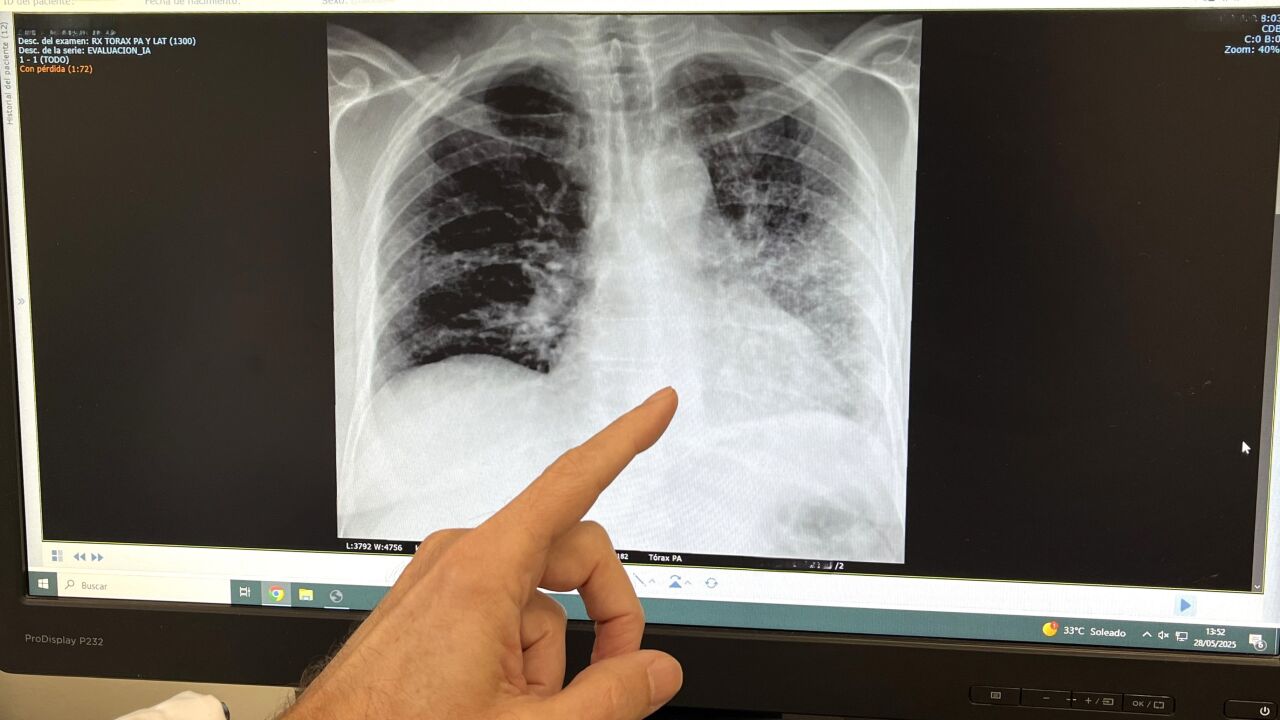

El tabaco es el responsable de más del 85% de los casos de cáncer de pulmón, así como de enfermedades como la Enfermedad Pulmonar Obstructiva Crónica (EPOC), bronquitis crónica y exacerbaciones del asma, según ha recalcado el doctor José Daniel Alcázar, jefe de servicio de Neumología del Hospital Quirónsalud Málaga. El doctor Alcázar ha afirmado que “en el Hospital Quirónsalud Málaga seguimos comprometidos con la prevención, el diagnóstico precoz y el tratamiento de enfermedades respiratorias vinculadas al tabaco”. Gracias a la incorporación reciente de la técnica EBUS (ecobroncoscopia), “damos un paso más en la detección y estadificación de enfermedades pulmonares, incluyendo el cáncer de pulmón, de forma mínimamente invasiva y con la máxima precisión diagnóstica”.